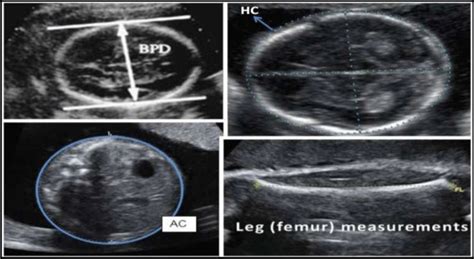

• BPD (Biparietal Diameter): This measures the distance across your baby’s head from one side to the other. It’s a crucial measurement to estimate the gestational age (how far along you are in your pregnancy) and the size of your baby. This measurement is super important because it helps doctors estimate how your baby is growing. They’ll look at it along with other measurements to get a good picture.

• HC (Head Circumference): As the name suggests, HC measures the circumference (the distance around) your baby’s head. It’s another important indicator of your baby’s head size and is often used alongside BPD to get a complete picture of your baby’s head development. HC is another important measurement because it tells doctors how big your baby’s head is. It is like measuring the head of your baby from the outside.

• AC (Abdominal Circumference): This measurement is all about your baby’s tummy! AC measures the circumference of your baby’s abdomen. It helps assess the size of your baby’s abdomen and can be an indicator of overall fetal growth and weight. This is very important to make sure your baby is growing well and is a healthy weight.

• FL (Femur Length): FL measures the length of your baby’s femur, which is the thigh bone. This measurement is helpful in estimating your baby’s overall size and can be compared with other measurements to assess proportionality. This helps doctors to see the length of the baby’s thigh bone.